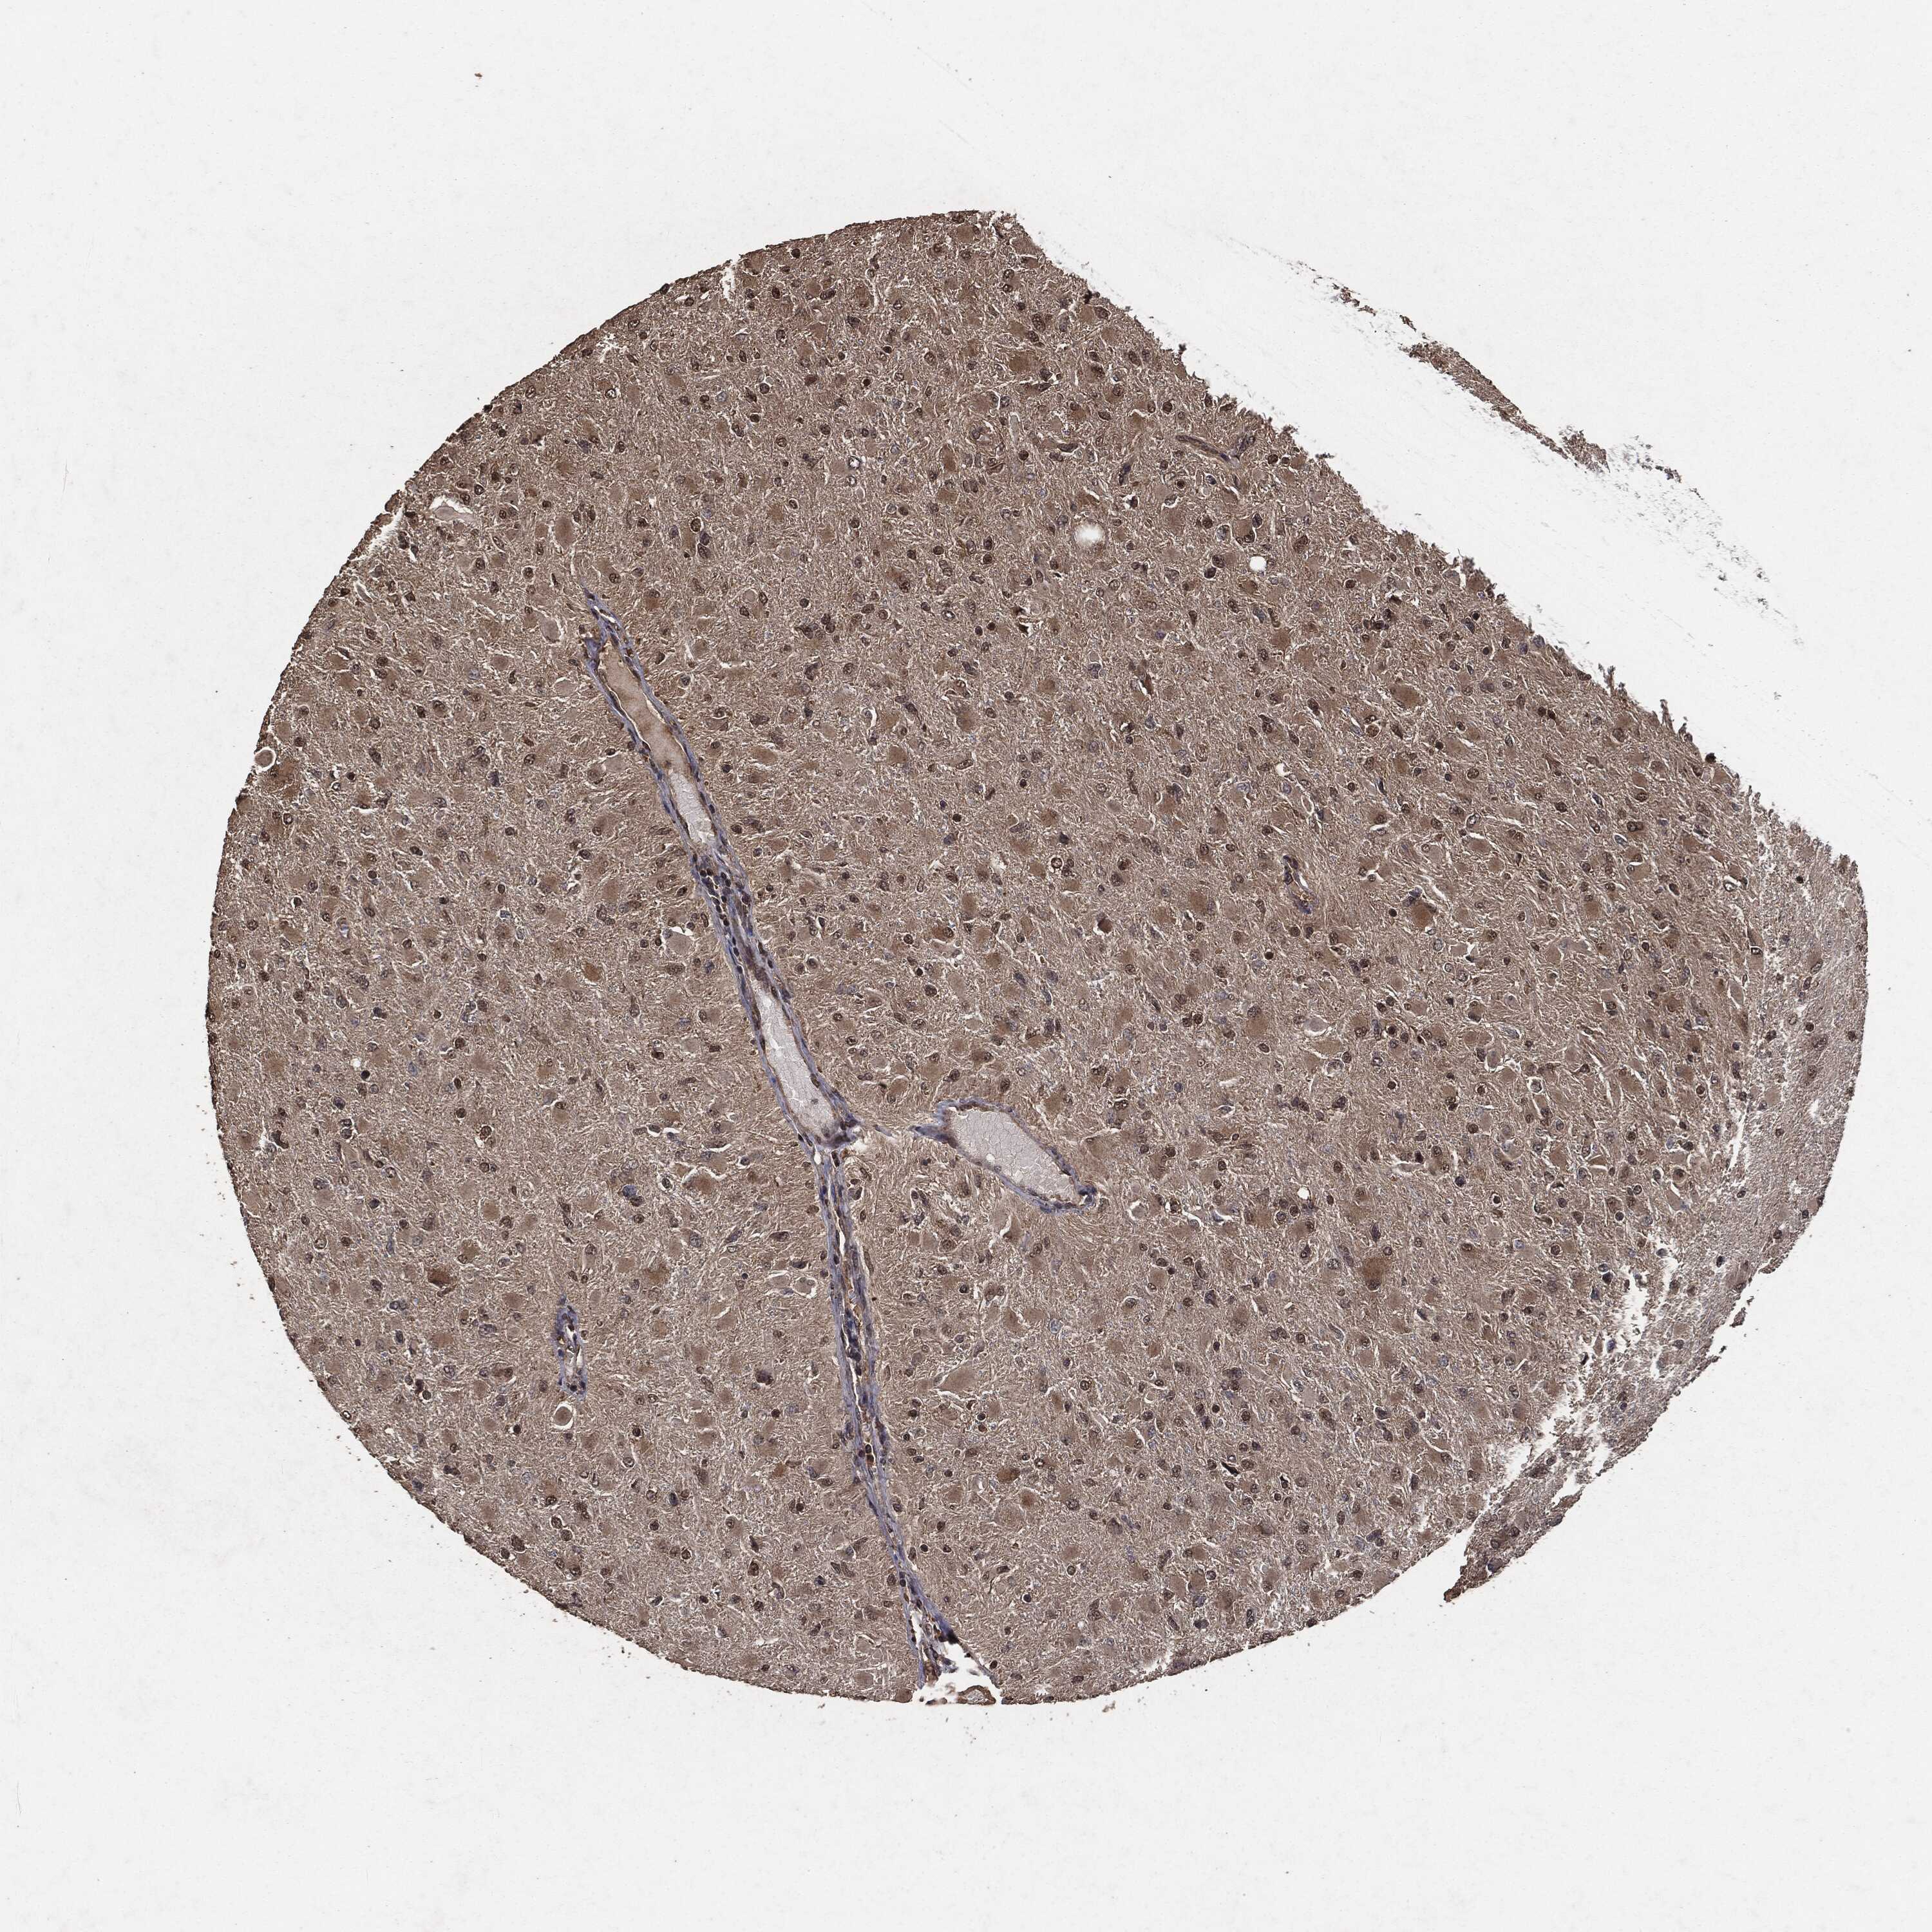

GLIOMA - Protein expressioni

A mouse-over function shows sample information and annotation data. Click on an image to view it in a full screen mode. Samples can be filtered based on level of antibody staining by selecting one or several of the following categories: high, medium, low and not detected. The assay and annotation is described here.

Note that samples used for immunohistochemistry by the Human Protein Atlas do not correspond to samples in the TCGA dataset.

Antibody stainingi

Antibody staining in the annotated cell types in the current human tissue is reported as not detected, low, medium, or high, based on conventional immunohistochemistry profiling in selected tissues. This score is based on the combination of the staining intensity and fraction of stained cells.

Each image is clickable and will lead to virtual microscopy that enables deeper exploration of all samples and also displays staining intensity scores, fraction scores and subcellular localization as well as patient and tissue information for each sample.

Antibody HPA064427

Antibody HPA075510

Antibody CAB021903

Staining

High

Medium

Low

Not detected

Intensity

Strong

Moderate

Weak

Negative

Quantity

>75%

75%-25%

<25%

None

Location

Nuclear

Cytoplasmic/membranous

Cytoplasmic/membranous,nuclear

Glioma, malignant, Low grade

Glioma, malignant, High grade